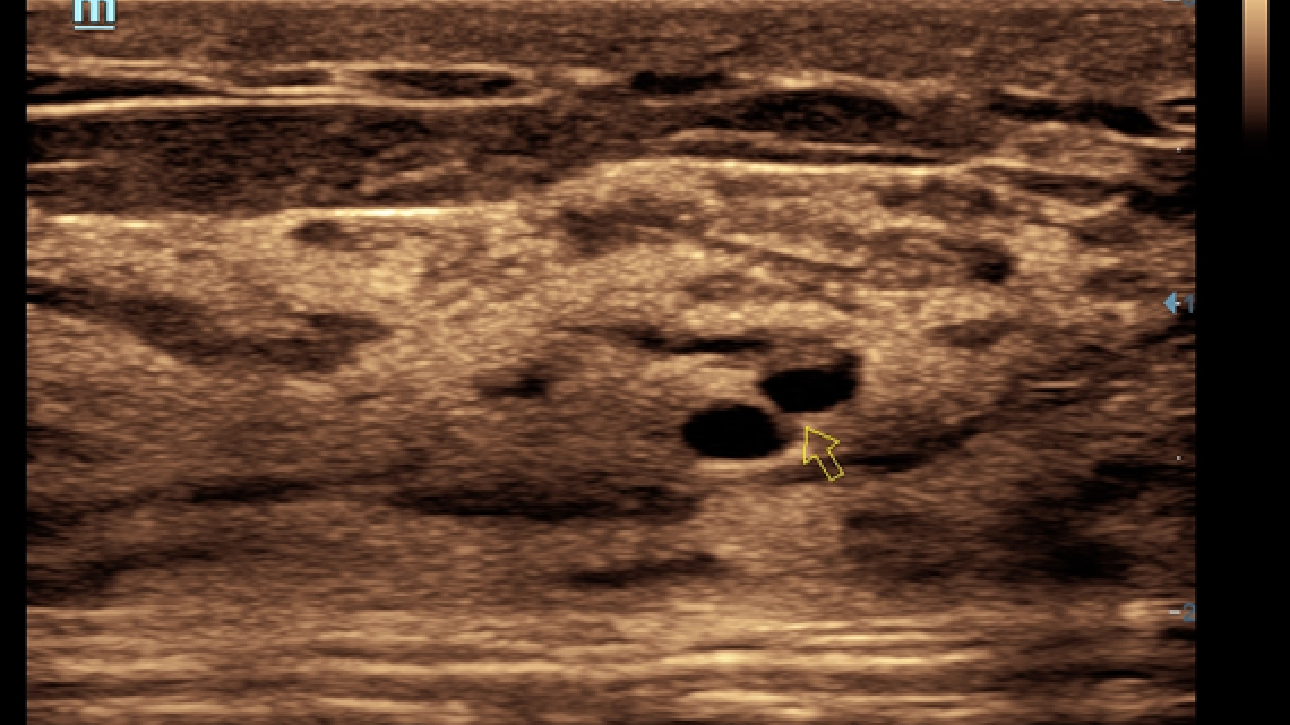

X-Insight ??? ??? ??? ??? ?? ??? ?? ?? ??????.

?????? ??? ???? ?? ???? ??? ??? ??? ???? ??? ??? ??? ?? ??? ???? ?????. ??? ?? ????? ???? ???? ??? ?? ??? ???? ?? ???? ??? ???? ???? ????.

???? ?? ??? ?????, X-Insight???? ??? DC-60 Exp ?? ??? ???? ???? ?? ??? ?? ??? ?? ???? ?????.

X-Insight??? ??? DC-60 Exp? ??? ??? ?? ?? ???? ???? ???(eXpress) ???, ???(eExceptional) ?????, ???? (eXceeding) ?? ??? ?? ????, ??? ???? ??? ??? ?? ???? ?????.